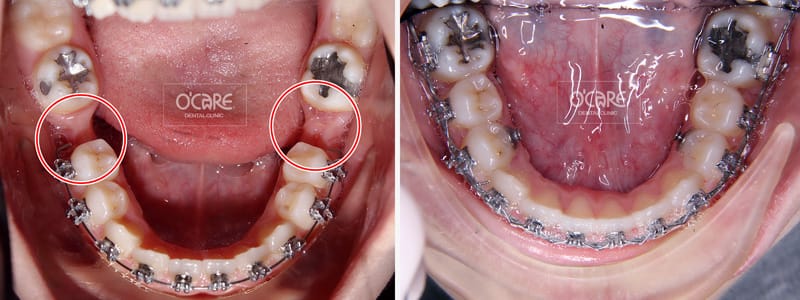

Niềng răng khi mất răng số 6 tại nha khoa Ocare

Cần bác sĩ chỉnh nha chuyên sâu để tránh nghiêng răng, lệch trục

Trong nhiều trường hợp, bác sĩ có thể kết hợp cả hai phương pháp:

Niềng răng để sắp xếp lại trục răng, tạo khoảng chuẩn

Sau đó cấy ghép implant để phục hồi răng số 6 đúng vị trí sinh lý